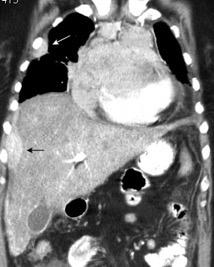

Carcinoma de mama con derrame pleural e implantes metastáticos

Makis W et al. Spectrum of Malignant Pleural and Pericardial Disease on FDG PET/CT. AJR. 2012